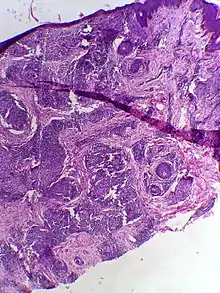

Skin biopsy in tuberculoid leprosy showing multiple peri-appendageal granulomas. | |

Tuberculoid leprosy is a form of leprosy characterized by solitary skin lesions that are asymmetrically distributed with few lesions and well demarcated edges. There is also early and marked nerve damage. It tends to heal spontaneously.[1]: 345 Tuberculoid leprosy is characterized by the formation of epithelioid cell granulomas consisting of a large number of epithelioid cells. In this form of leprosy, Mycobacterium leprae are either absent from the lesion or occur in very small numbers. This type of leprosy is the most benign and the least contagious.[2][3]